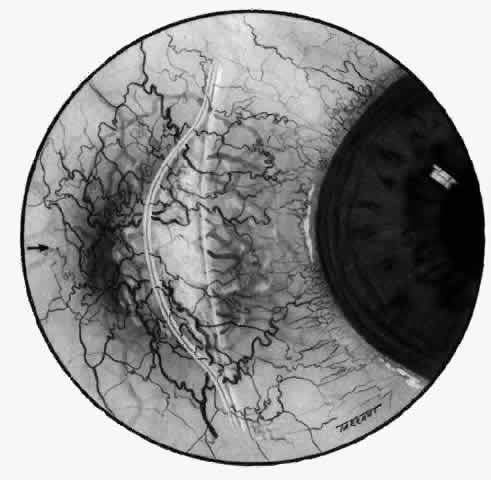

of the eye. A posterior scleritis often occurs as an extension of anterior

disease; but, as in Figure 20, most of the inflammation (in some cases all of the inflammation) is in

the posterior segment and the exudative detachments and subretinal granulomas

can be mistaken for malignant melanoma.  Fig. 19. Anterior necrotizing scleritis. The eye was removed because of loss of

vision and intractable pain. No form of steroid was given to this patient

because of a severe Pseudomonas infection of the chest. (Courtesy of Professor N. Ashton) Fig. 19. Anterior necrotizing scleritis. The eye was removed because of loss of

vision and intractable pain. No form of steroid was given to this patient

because of a severe Pseudomonas infection of the chest. (Courtesy of Professor N. Ashton)

|

Fig. 20. Posterior scleritis. This eye was removed because of loss of vision and

pain, mistakenly diagnosed as malignant melanoma. (Courtesy of Professor N. Ashton) Fig. 20. Posterior scleritis. This eye was removed because of loss of vision and

pain, mistakenly diagnosed as malignant melanoma. (Courtesy of Professor N. Ashton)

|

scleritis. Posterior Scleritis Because the posterior sclera is invisible, the diagnosis of posterior scleritis

is made only if the anterior sclera is also involved or some

other sign or symptom leads one to suspect it. Posterior scleritis is

much more common than previously suspected, as recent clinical and pathologic

studies have shown.19,28,29 There are two distinct forms of posterior scleritis. The first is usually

associated with an anterior scleritis. This granulomatous disorder, like

its anterior counterpart, can be diffuse, nodular, or necrotizing

in character and is associated with the connective tissue diseases. The

second form occurs in young patients of all races who are 9 to 40 years

of age. It is always diffuse in character but is not associated

with any systemic disorder. Both forms may cause uveitis if the inflammation

affects the ciliary body, and in both forms the patient may develop

exudative retinal detachments, choroidal folds, and swelling of

the disc (Figs. 51 and 52). The granulomatous type may also involve the structures outside the globe, causing

proptosis (Fig. 53), limitation of ocular muscle movement, and, uniquely, retraction of the

lower lid on attempted elevation of the eye (Fig. 54). Diagnosis is with B-scan ultrasonography.  Fig. 51. Swelling of the optic nerve head and hemorrhage near the disc in a patient